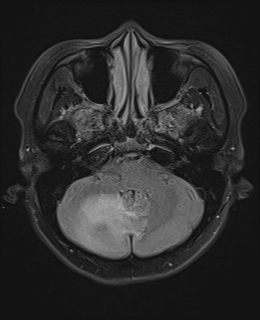

@SharathKumarGG7 Great summary, hopefully notebookLM improves in the future - the FLAIR images seem to be dodgy

Enhanced myometrial vascularity is not a uterine AVM. This review clarifies definitions, key Doppler/MRI findings & management to avoid unnecessary embolization, hysterectomy & complications in post pregnancy bleeding. @StanfordBodyRad @stanfordRad bit.ly/463EX7M